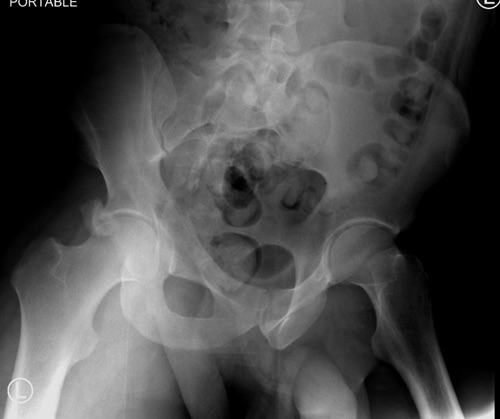

Данная картина показывает очень редкий перелом передней колонны, но

перед операцией еще раз надо просмотреть обещанные дополнительные КТ срезы.

Представленные слайды Александром из Севастополя, имеет ценность, но,

кроме inlet, остальные стандартные Judet рентген снимки должны показать

правоту принятого решения. Возможно, здесь фиксация перелома вертлужной

впадины, но по рентгену трудно понять!